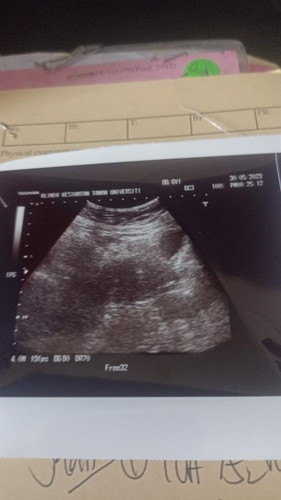

Kembali hamil!

syukur saya hamil semula lepas 3 tahun!♥️

alhamdulillah. .thniahh....tp nk tnya..kntung blah kanan atas tu ke?

Dah berapa minggu puan? Alhamdulillah tahniah